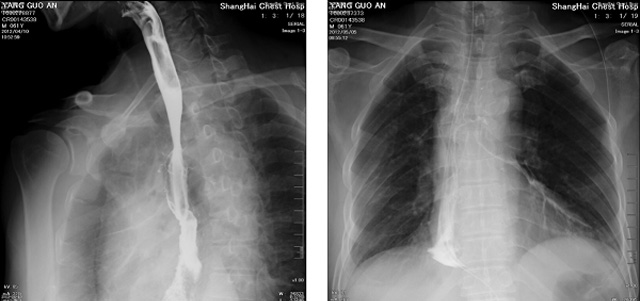

DR設備在2020年的新冠疫情中,加速了市場調整。以醫院為主的向二三級市場轉變。特別是小巧靈活的移動DR設計,填補CT和磁共振不能三維檢查的缺點,滿足內科外科特別是骨科的影像診斷需求。還有懸吊DR設備CT斷層射線系統。使用錐束成像技術對整個脊柱和整個下肢進行了體積三維掃描。無需使用對比劑,即可使用X射線呼吸功能標測來模擬模擬氣流和血流,以評估患者的肺動脈血栓。